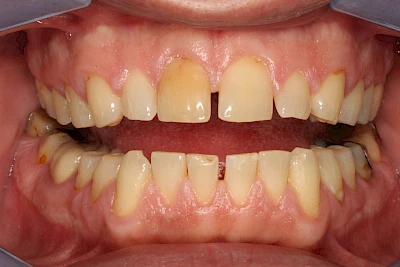

Von außen (exogen) eher dunkel gefärbt und meist mehrere Zähne betroffen:

- Genußmittel (Tee, Kaffee, Rauchen)

- Medikamente (z. B. Eisen)

Äußere Verfärbungen durch Genußmittel oder Medikamente (Eisen!) lassen sich meist nur durch den Zahnarzt z. B. mit einer professionellen Zahnreinigung entfernen.